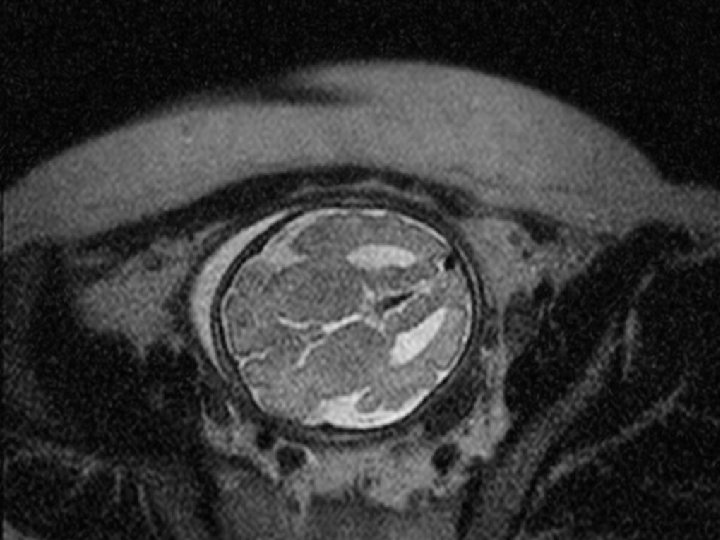

Normal MRI T 2 Weighted